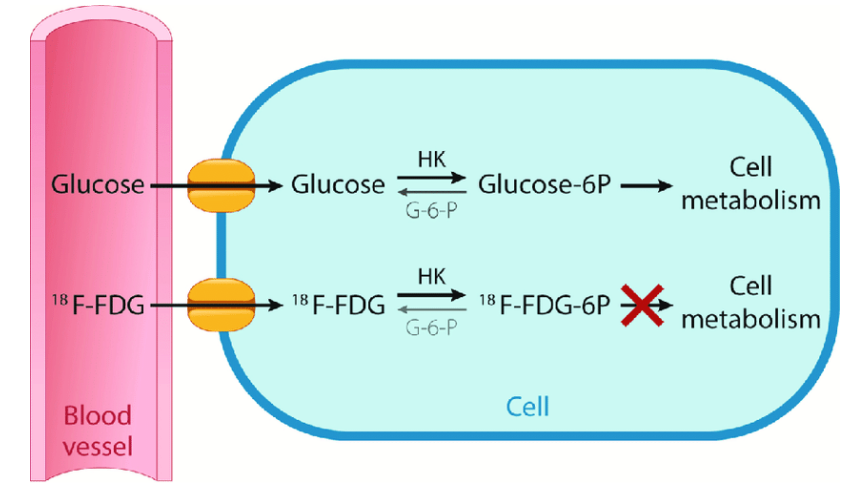

Why do we like to use FDG as a pharmaceutical in PET?

It’s a sugar that is very similar to glucose

As cancer uses metabolic processes, it uses glucose as its main form of energy – we take advantage of this by binding the radioactive material with a pharmaceutical that’s similar in structure to glucose so that we can visualize where the cancer is based on its metabolism

What happens to the FDG when it’s up-taken by the cancer cells?

Instead of breaking down FDG and using it as energy, it will just accumulate in the cancer cell – makes the cancer more visible on our PET images